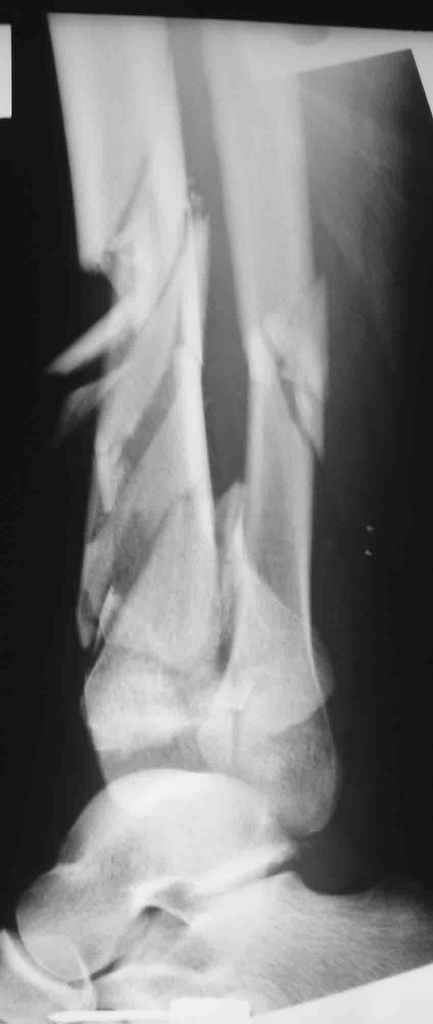

Мне кажется, что все дискутирующие согласным с одним - надо воостанавливать в данной ситуации суставную поверхность. Сделать это закрыто (когда суставная поверхность состит из 3-фрагментов)лично для меня не реально. Конечно можно открыто отрепонировать, зафиксировать спицами и оставить в аппарате, но роль аппарата и выполняет LSP. Разрез в области внутренней поверхность голеностопного сустава и небольшой разрез в ср/3 голени для проксимальных винтов, надкостница не обдирается, пластина вводится подкожно.

Вид конечности на следующий день после операции.

Наверно не дошел, вот еще раз.

8.jpg

14KB (14977 bytes)